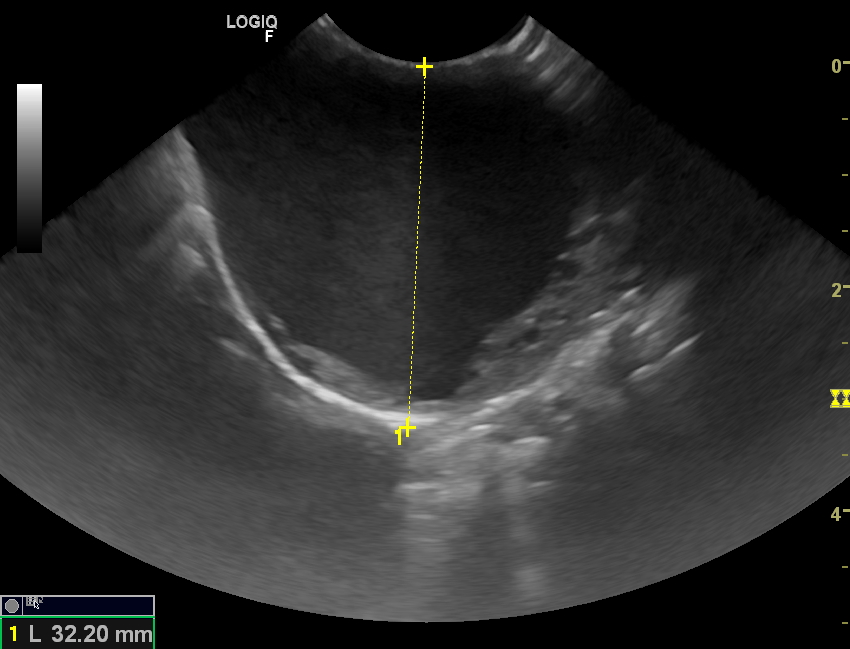

USG vyšetření ukázalo, že se nejedná o nádor, ale o tenkostěnnou cystu (tekutina se zobrazuje černě)